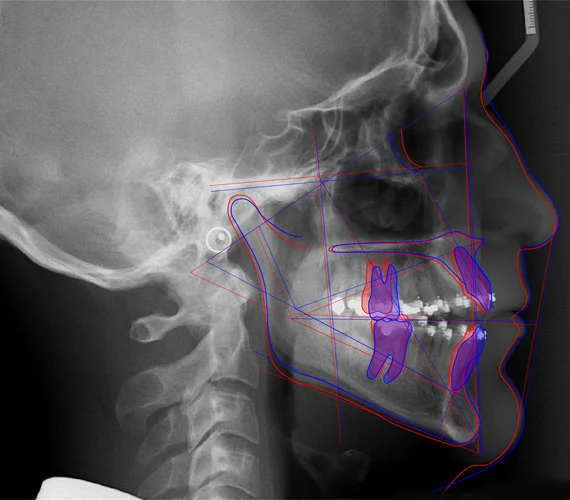

Cas 1 : Classe II Division 1 Squelettique

Données céphalométriques :

- SNA : 82° (légèrement augmenté)

- SNB : 74° (nettement diminué)

- ANB : 8° (très augmenté – classe II squelettique marquée)

- FMA : 24° (normal)

- Convexité : 6 mm (augmentée)

- I/F : 115° (vestibulo-version des incisives supérieures)

- Ls/E : +3 mm (forte protrusion labiale supérieure)

Diagnostic : Classe II squelettique par rétrognathie mandibulaire avec compensation dento-alvéolaire (vestibulo-version des incisives supérieures).

Options thérapeutiques :

- Chez l’enfant en croissance : appareil fonctionnel pour stimuler la croissance mandibulaire

- Chez l’adulte : orthodontie avec extractions ou chirurgie d’avancement mandibulaire

- Dans tous les cas : contrôle de la vestibulo-version des incisives supérieures